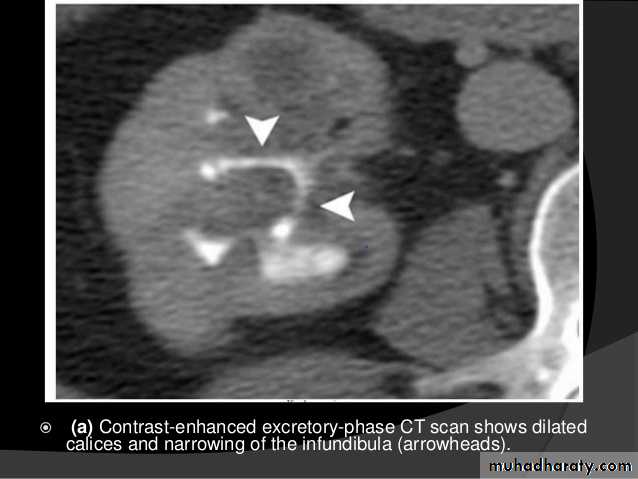

Computed Tomography